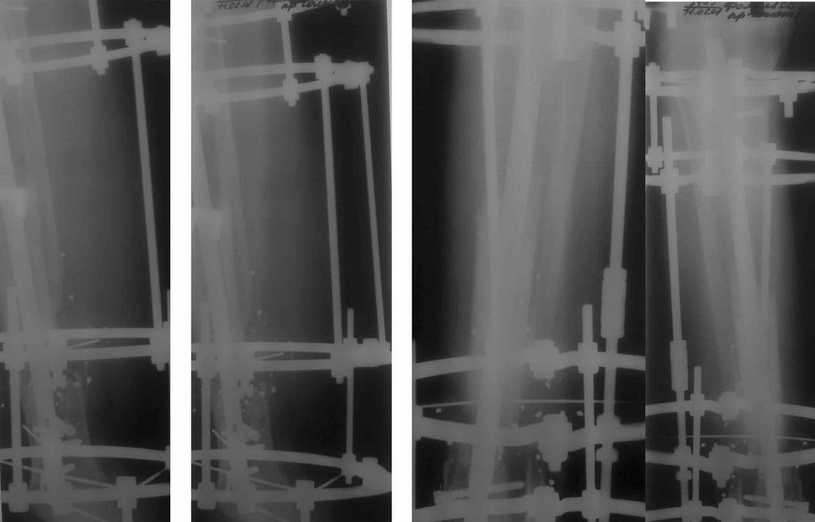

Пример (пациент 46 лет, лечился у нас 4 года назад, внутренний остеосинтез выполнен с определенными погрешностями, но перелом сросся и рецидива инфекции не было): рис. 1,2 - при переводе к нам в институт, рис. 3 - после микрохирругической пластики, рис. 4, 5 - после интрамедуллярного остеосинтеза, рис. 6, 7, 8 - внешний вид и рентгенограммы после окончания лечения

Больному была выполнена операция. после демонтажа аппарата Илизарова столкнулись с "прямо на глазах" сокращением регенерата. Гвоздь сквозь регенерат удалось провести без технических трудностей. Сложности были с репозицией отломков, что связано с выраженным остеопорозом, их короткими размерами. Пришлось применить полер-винт. Выполнили блокирование. По причине укорочения регенерата пришлось повторно смонтировать аппарат Илизарова и начать транспорт фрагмента на гвозде (14 мм). Больному разрешена ходьба с дозированной нагрузкой на больную ногу. Контрольные рентгенограммы прилагаются. Нынешняя ситуация породила ряд вопросов и замечаний:

1)Как долго удерживать аппарат без риска повторного укорочения регенерата?

2)Когда можно будет разрешить полную нагрузку на больную конечность?

3) Нам видится, что больной уже с момента постуления должен "вестись" по стандартизированному протоколу, чтобы избежать тех трудностей с которыми столкнулись мы в момент операции. Существует ли подобное у вас?

4)Выполнял ли кто-нибудь замещение дефекта кости транспортом фрагмента по Илизарову на гвозде?

5)Считаем необходимым наличие промежуточных отверстий в гвозде для блокирования фрагмента, чтобы воспрепятствовать укорочению регенерата.